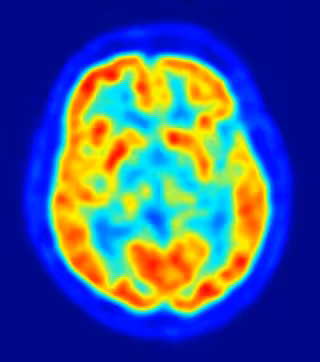

Después, todas estas personas pasaron por imágenes de resonancia magnética, con las que se construyeron mapas muy exactos de su cerebro. Los investigadores utilizaron estos mapas para medir el volumen de las diferentes regiones del cerebro y consideraron si los tamaños de estas regiones podían predecir la vergüenza que sentían los participantes.

Descubrieron que las personas que tenían una neurodegeneración significativa en la corteza cingulada anterior pregenual eran menos propensos a sentir vergüenza. De hecho, a mayor deterioro del tejido de esta parte del cerebro, menor era la vergüenza que las personas sentían al escuchar su canción.